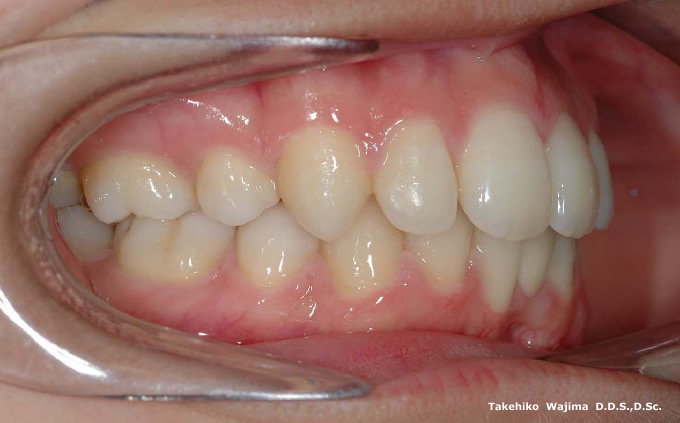

| 口腔内所見 | オーバージェット 16.0mm、over bite 9.0mm、臼歯関係Ⅰ級、下顎前歯部に先天欠如歯が認められ、下顎正中は左側へ3.0mm偏位していた。 |

| 批評・予後 | 治療計画として、A点はホールド、若干の大臼歯部の前方へのロスはやむを得ないもののチンコントロールの為に、垂直的ロス(挺出)を可及的に防止する。 また、上顎前歯部は上顎両側第一小臼歯抜歯スペースを最大限に利用し後退させ、下顎前歯部はスピー弯曲の除去と唇側傾斜によりオーバージェットの改善を行意顔貌、咬合の改善を行う。ほぼ満足のいく結果が得られた。 |